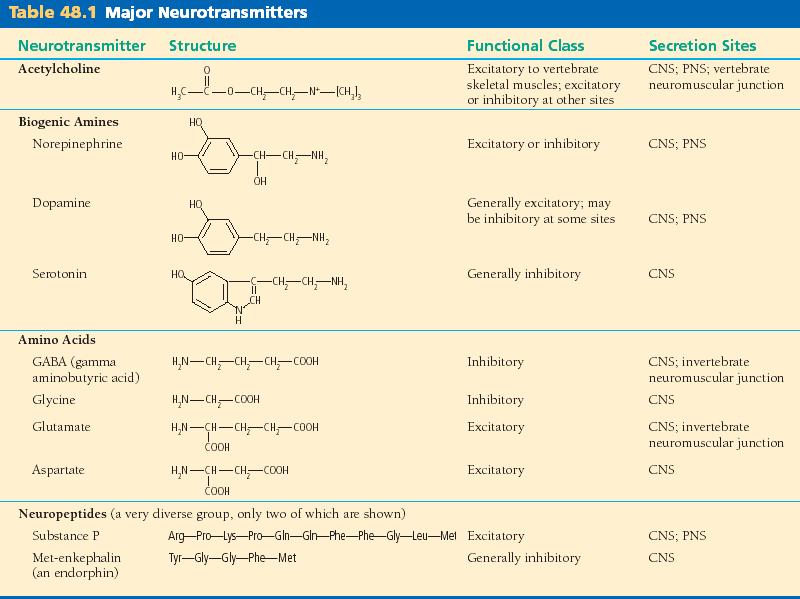

48_01Neurotransmitters_T